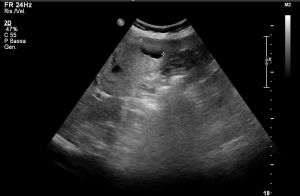

Ad oggi sono state identificate con l’ecografia addominale prevista dal protocollo, 9 neoplasie del parenchima epatico: 5 angiosarcomi (Fig. 1-4) (di cui 2 viventi) e 4 epatocarcinomi (Fig. 5-7) (di cui 1 vivente), successivamente sottoposte a studio TC e tutte confermate dalla diagnosi istologica.

Fig.5. Caso di HCC

Fig.6. Caso di HCC

Fig.7. Caso di HCC